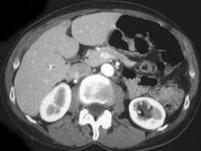

问题 女,38岁,无特殊临床表现,根据影像,选择最有可能的诊断 ( )

选项 A、左肾高密度囊肿 B、左肾单纯性囊肿并感染 C、左肾单纯性囊肿 D、左肾钙化性囊肿 E、左肾癌

答案 A